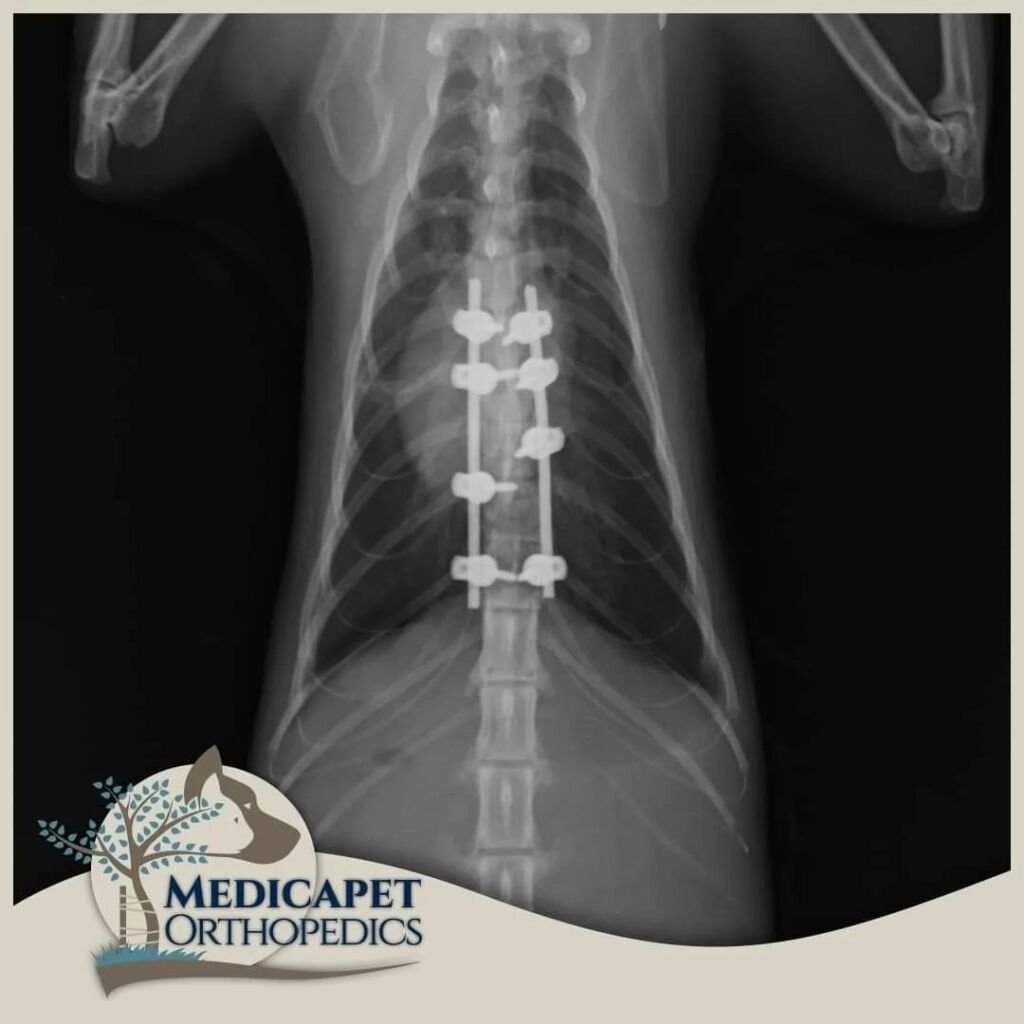

Kemik dokulara paralel seyreden ya da onların içinde bulunan sinir yapıları, kemik hasarlarıyla birlikte zarar görebilir. Yumuşak yapılı sinir dokuları en küçük travmaya karşı hassastır ve korunmaya ihtiyaç duyar. Beyin ve omurilik gibi organlar kafatası ve omurga tarafından korunur, bu nedenle kemik dokuların tedavi ve onarımı sinir dokusuna zarar vermeden yapılmalıdır. Ayrıca bazı sinir hastalıklarında da (örneğin tümörler) kemik dokuya müdahale gerekebilir. Bu yüzden nöroloji ve ortopedi yakından ilişkilidir.

Sinir sistemi; Merkezi Sinir Sistemi (beyin, beyincik, beyin sapı, omurilik) ve Periferik Sinir Sisteminden (gangliyonlar, sinirler, sinir uçları) oluşur. Kliniğe başvuran hastaların çoğunda trafik kazaları, düşme, saldırılar gibi nedenlerle omurga kırıkları, kafatası travmaları veya felç durumları görülmektedir. Bazı ırklarda genetik yatkınlık da omurga sorunlarına yol açabilir.

Nörolojik cerrahide operasyon kadar öncesi ve sonrası bakım da önemlidir. Operasyon sonrası ödem sinir dokularda bası oluşturabileceğinden dikkatli cerrahi, uygun ilaç tedavisi ve gerektiğinde fizik tedavi süreci titizlikle uygulanmalıdır. Sinir dokusu diğer dokulara göre çok daha yavaş iyileşir; küçük bir kesik deride kısa sürede düzelirken omurilikte kalıcı felce yol açabilir.